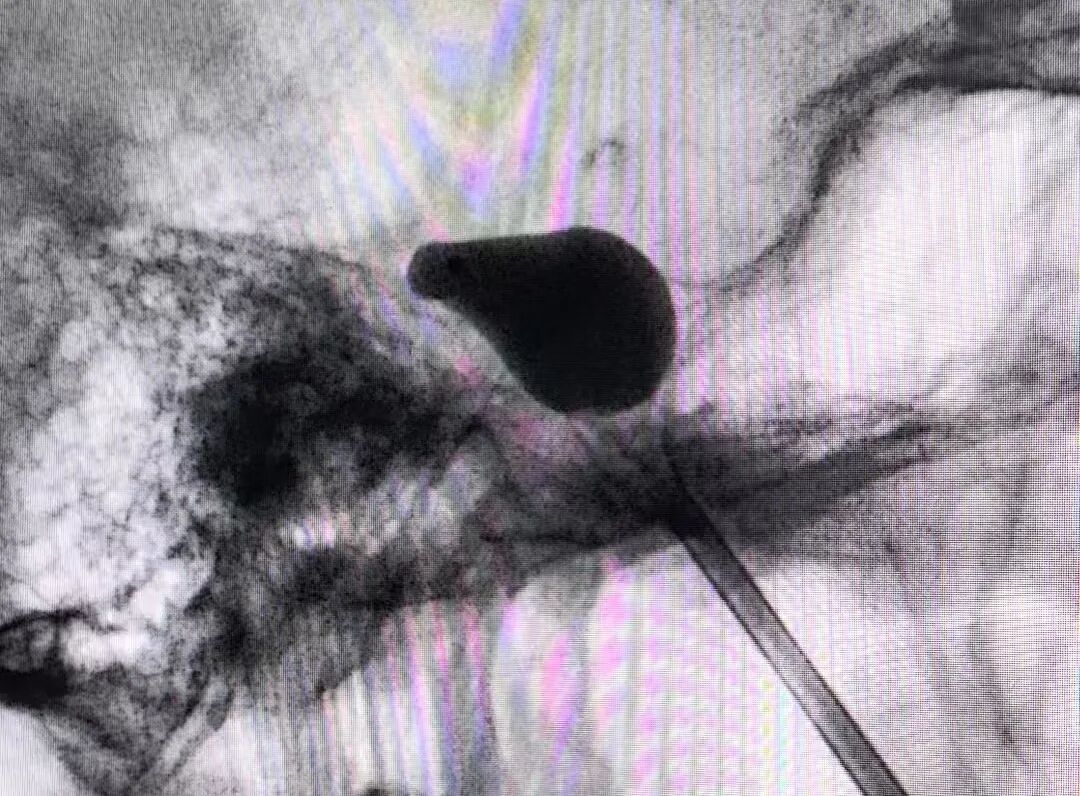

经过反复权衡利弊,并与患者家属全面深入沟通后,医疗团队做出了大胆决策——先行实施“经皮穿刺三叉神经半月节球囊压迫术(PBC)”来治疗三叉神经痛。神经外二科姜海涛教授解释,PBC是一种微创手术,通过面部穿刺一个针眼,在X线引导下将球囊导管送至颅内负责面部感觉的三叉神经半月节,然后充盈球囊有控制地压迫神经,从而阻断疼痛信号的传导,具有手术时间短、术后恢复快的优点。

手术中,主刀医师凭借丰富的经验和稳定的手感,在影像引导下轻柔、缓慢地进行穿刺操作,力求将对神经的刺激降到最低。麻醉医生紧盯监护屏幕,实时汇报血压、心率数据。手术团队与麻醉医生之间指令清晰,配合默契。血压高时暂停操作,调整节奏;麻醉医生精准用药,稳定血压。在充分的预案和团队紧密协作的保驾护航下,患者生命体征始终稳稳控制在安全范围内,整个手术过程如预期顺利结束。